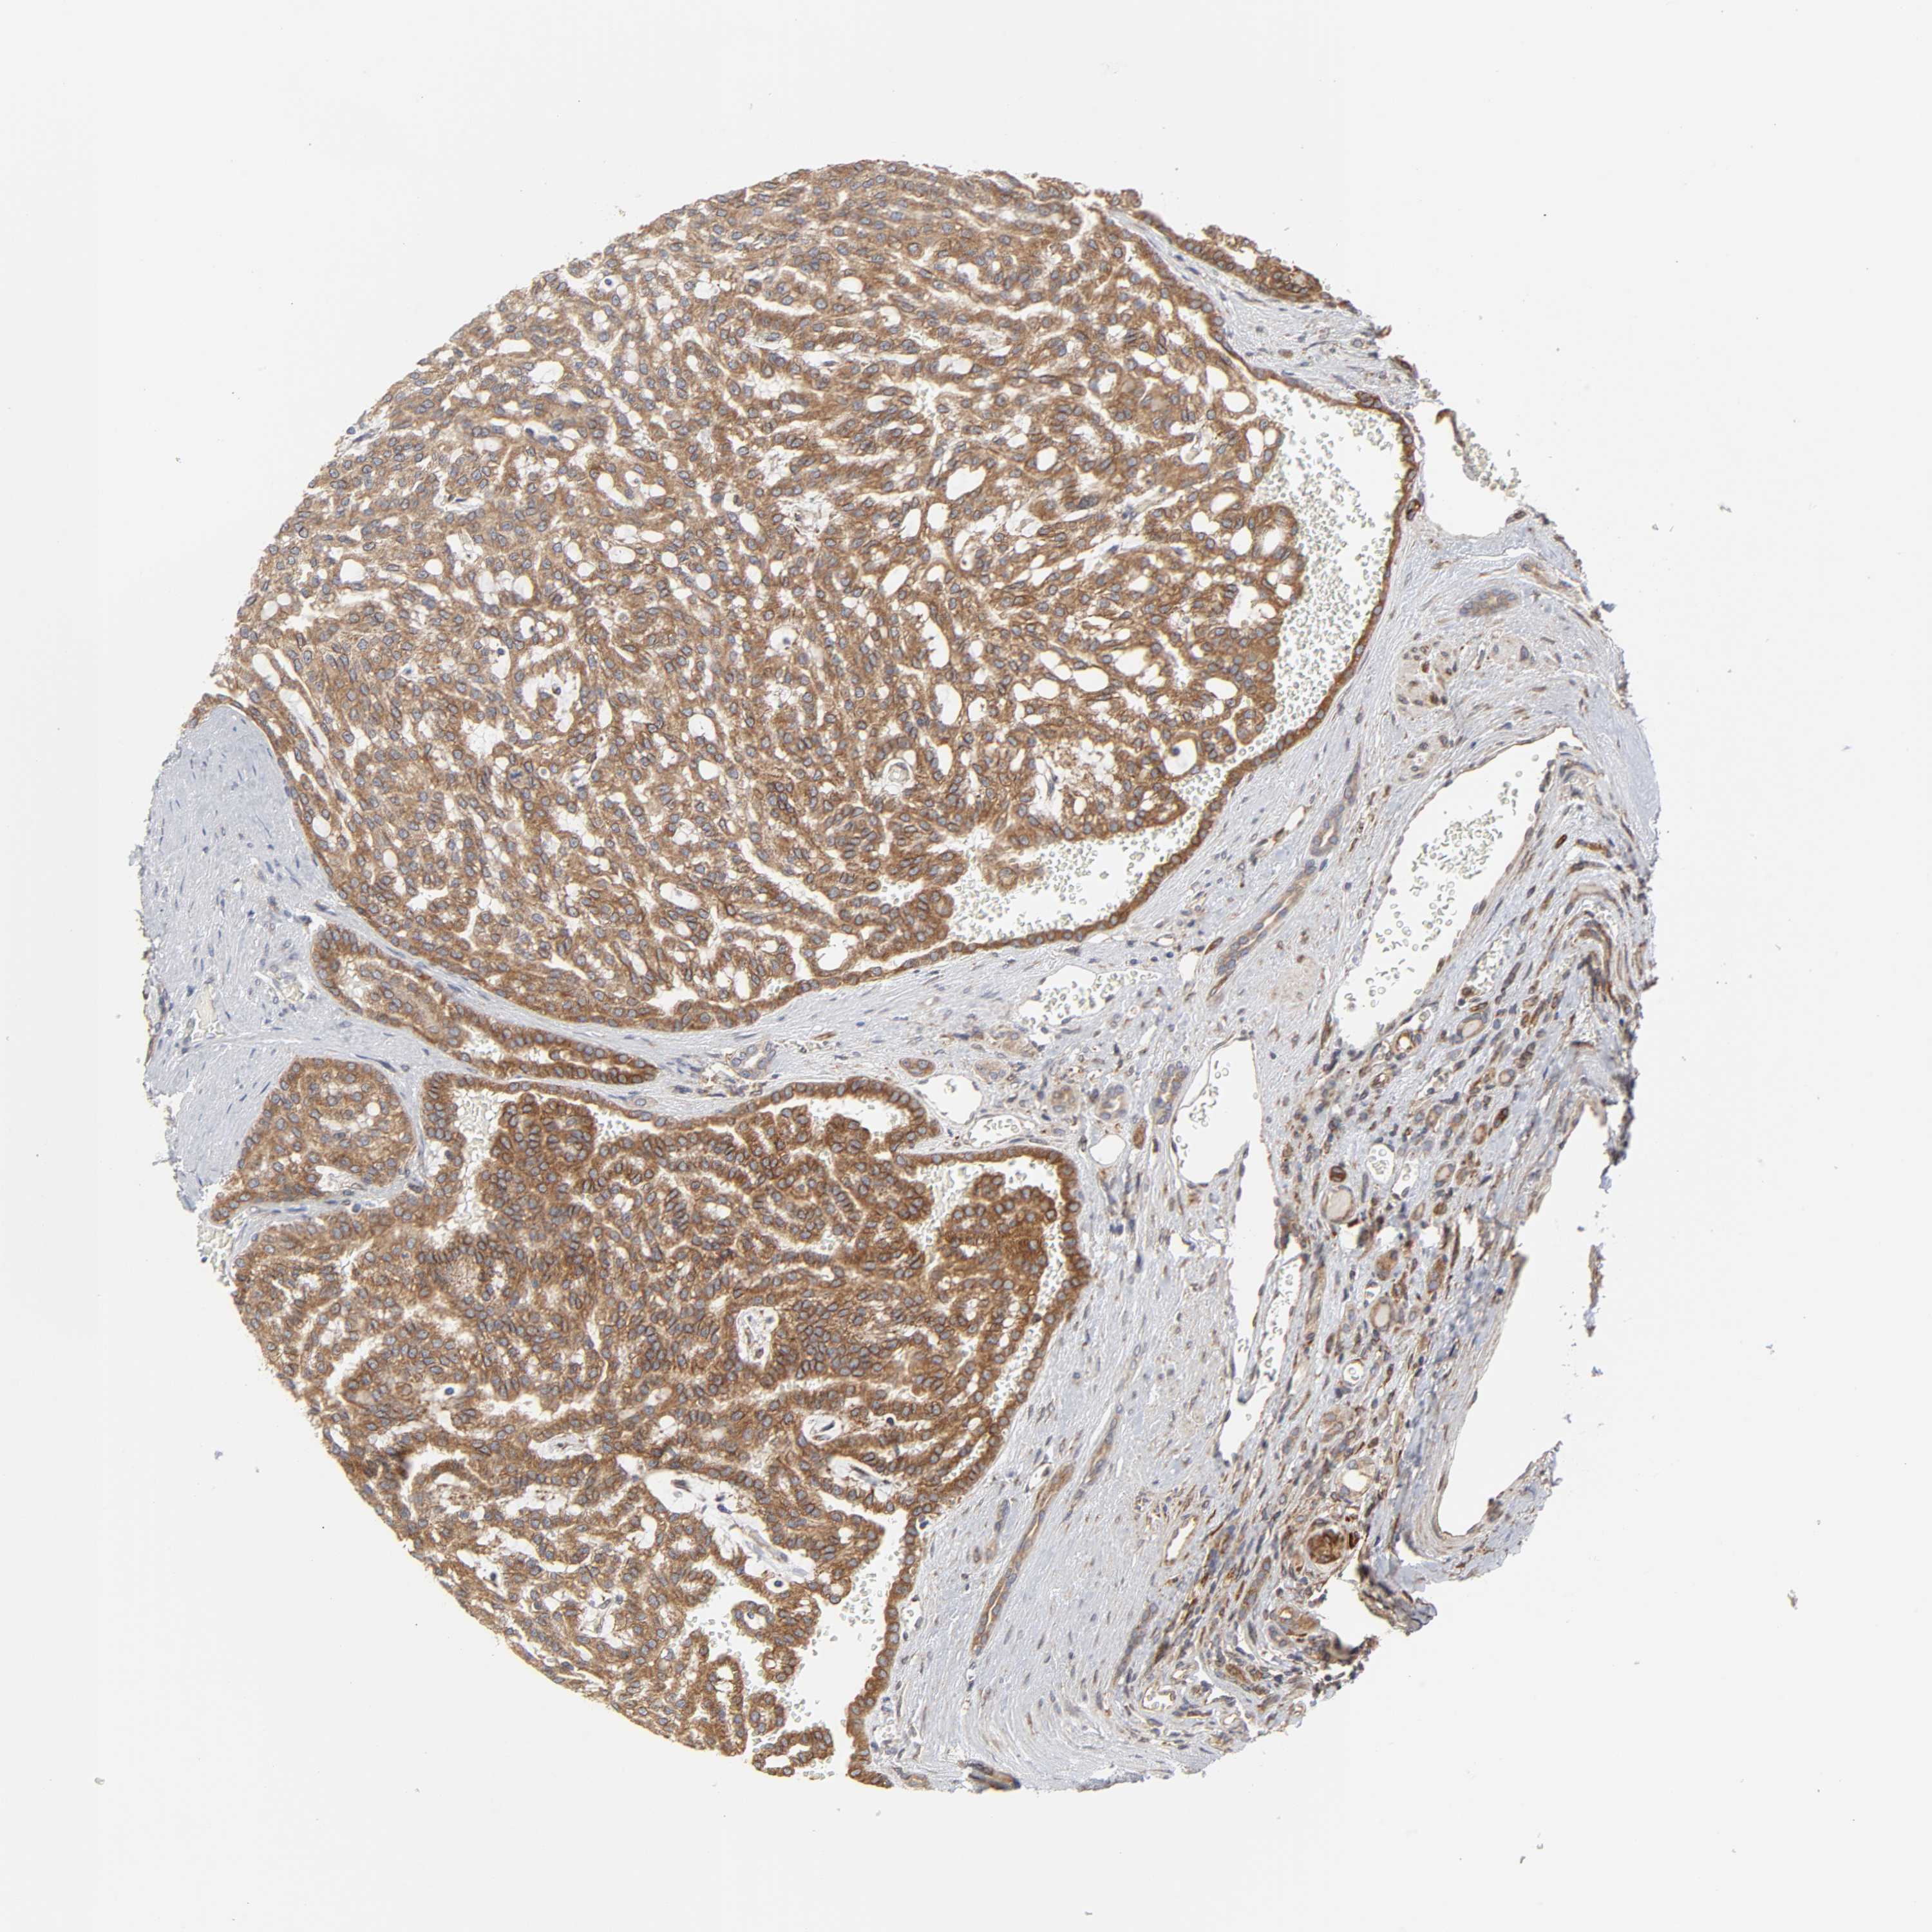

KIDNEY RENAL PAPILLARY CELL CARCINOMA (TCGA) - Interactive survival scatter ploti

The Survival Scatter plot shows the clinical status (i.e. dead or alive) for all individuals in the patient cohort, based on the same data that underlies the corresponding Kaplan-Meier plots. Patients that are alive at last time for follow-up are shown in blue and patients who have died during the study are shown in red.

The x-axis shows the expression levels (FPKM) of the investigated gene in the tumor tissue at the time of diagnosis. The y-axis shows the follow-up time after diagnosis (years). Both axes are complimented with kernel density curves demonstrating the data density over the axes. The top density plot shows the expression levels (FPKM) distribution among dead (red) and alive patients (blue). The right density plot shows the data density of the survived years of dead patients with high and low expression levels respectively, stratified using the cutoff indicated by the vertical dashed line through the Survival Scatter plot. This cutoff is automatically defined based on the FPKM cutoff that minimizes the p-score. The cutoff can be changed by dragging the vertical line or by entering a cutoff value in the square labeled "Current cut-off".

Under the Survival Scatter plot the p-score landscape (black curve; left axis) is shown together with dead median separation (red curve; right axis). Dead median separation is the difference in median mRNA expression between patients who have died with high and low expression, respectively. It is calculated as follows: median FPKM expression of dead patients with high expression - median FPKM expression of dead patients with low expression. This is intended to aid the user in visually exploring custom cutoffs and the associated p-scores and dead median separation.

Individual patient data is displayed and can be filtered by clicking on one or more of the category buttons on the top of the page. Categories describing expression level and patient information include: high, low, alive, dead, female, male and tumor stages. The scale of the x-axis can be toggled between linear and log-scale by clicking on the "x log" button. Mouse-over function shows TCGA ID, patient information and mRNA expression (FPKM) for each patient.

& Survival analysisi

Kaplan-Meier plots summarize results from analysis of correlation between mRNA expression level and patient survival. Patients were divided based on level of expression into one of the two groups "low" (under cut off) or "high" (over cut off). X-axis shows time for survival (years) and y-axis shows the probability of survival, where 1.0 corresponds to 100 percent.

POR is not prognostic in Kidney Renal Papillary Cell Carcinoma (TCGA)